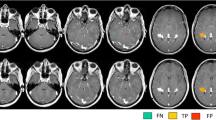

The mean number (SD) for overall amount of lesions scored per patient was 88.8 (67.8) on 3D-DIR, 100.4 (72.3) on 3D-FLAIR, 77.8 (54.6) on 3D-T2, 83.5 (71.9) on 3D-MPRAGE, and 82.4 (60.6) on 2D-T2SE images. The mean numbers per anatomical area, including statistical differences, are listed in Table 2. The highest numbers of intracortical and mixed WM-GM lesions were scored on 3D-DIR (Fig. 2). Both findings were significantly higher compared to 2D-T2SE (p = 0.036 and p = 0.019, respectively). By comparison, the lowest number of juxtacortical lesions was seen on 3D-DIR, whereas the most were scored on 2D-T2SE images; however, this difference was not significant (p = 0.086). The highest number of WM lesions was scored on 3D-FLAIR, which was significant compared to 2D-T2SE (p = 0.002). 3D-DIR showed the smallest number of deep WM lesions, although not significantly compared to 2D-T2SE. Both 3D-DIR and 3D-FLAIR, although not significant when compared to 2D-T2SE (p = 0.237 and p = 0.173, respectively), showed the highest detection of infratentorial lesions (Fig. 3).

Four axially reformatted images from an MS patient, no contrast applied. A: 3D-DIR, B: 3D-FLAIR, C: 3D-T2, and D: 3D-MPRAGE (sequence parameters are listed in Table 1). Images show several gray matter and white matter lesions. Straight arrows point out a juxtacortical lesion. Delta arrows point out a mixed WM-GM matter lesion that invades the cortical mantle. Arrowheads point out an intracortical lesion clearly seen on 3D-DIR and to a lesser extent on the other images